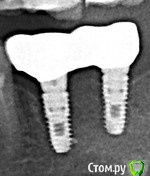

Наталия1966 Опубликовано 6 октября, 2019 Автор Поделиться Опубликовано 6 октября, 2019 (изменено) Да мне кажется, что тему закрыть можно. Топикстартер с тем же успехом может сама с собой говорить.Ну, вообщем, да, можно закрыть. Но мне было бы интересно дождаться результата установки. Все не так просто, как нам кажется с первого взгляда и случаи разные бывают. В принципе, в принципе... выдавливание гноя помогло и очень. Сегодня я проснулась и первым делом ощупка языком места - десна абсолютно ровная, потом побежала к зеркалу - гнойник ушел на его месте еще не совсем срослось и мягкий небольшой провальчик в месте гнойника, то есть заживает! Я сама еще пальцем слегка помассировала все вокруг от зуба до зуба -выдавилась еще капля гноя и все совсем опало. Десна розовая, ничего не болит. Заодно промассировала другой имплант, где мне в воспаленье вкрутил врач, он не болит, но нажим на десну и отпускание сильную пульсацию без боли вызывало. Там обмассировала и вот результат - десна лучше прилипать стала и пульсация исчезла! Вывод - никогда не надо торопиться, принимать поспешных решений. Если есть регламент - выжидать, значит нарушать его не надо 9 октября будет ровно 4 месяца. А на таком расщеплении гребня, видите, только только нормализовалось и то с вмешательством врача по десне. Нижние зубы не могут сливать сами гной как верхние, где он просто оттекал бы вниз. Тут вероятно он копиться в челюсти и не может сам исчезнуть. Вот такие пироги. Всем спасибо за внимание и добрые пожелания. Вот этим двум имплантам в июне ровно год был. Снимок в конце августа сделали. Одиночному верхнему год в ноябре будет. Изменено 6 октября, 2019 пользователем Наталия1966 Ссылка на комментарий

Наталия1966 Опубликовано 1 ноября, 2019 Автор Поделиться Опубликовано 1 ноября, 2019 (изменено) Ну, вот и все. Установлен формирователь. Снимок показал частичное обнажение импланта по передней стенке, задняя покрывает весь имплант. Доктор сказал, что в принципе это допустимо. Если не будет нагноения в передней части импланта, то считайте, что он установлен. Если будет постоянное нагноение, то два варианта - удаление самого импланта, либо попытка подсадки кости на переднюю стенку. Посмотрим, конечно. Я что думаю. Если часть импланта обнажена, то не будет ли зубной камень лепиться к этой части, тело импланта не полировано. Мож отполировать как-то. Тогда прирастет ли десна. Вообщем пока два варианта - удаленье (очень не хотелось бы) и костная пластика. 10-мм имплант утоплен по край сзади и где-то на 5-6 мм спереди. Вот такие пироги! Изменено 1 ноября, 2019 пользователем Наталия1966 Ссылка на комментарий